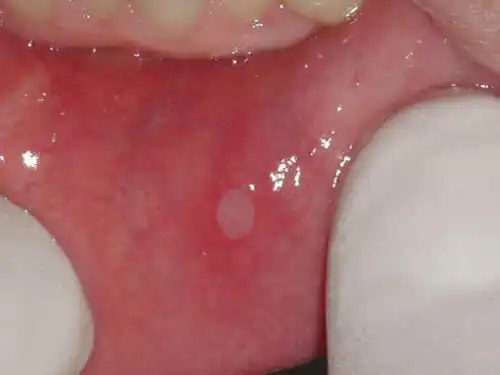

De obicei, apare o singură leziune rotundă, de culoare albicioasă, înconjurată de o zonă inflamată. Rareori aftele bucale sunt mai mari de o,8 cm.

În plus, pot apărea mai multe răni deodată, acestea fiind adesea mai mici de 0,8 cm. De asemenea, există cazuri în care aceste leziuni sunt mai mari, iar vindecarea este mai complexă.